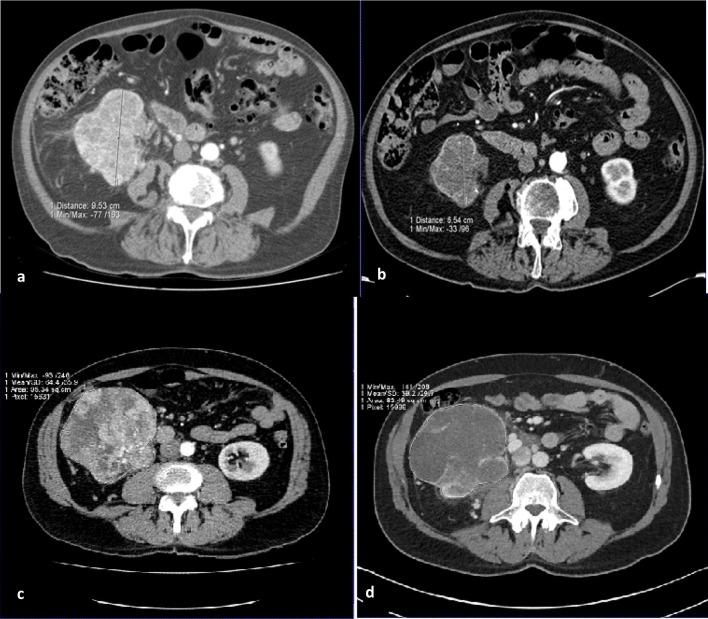

RESULTS

Characterisation of small renal masses (SRM) remains a diagnostic conundrum. Contrast-enhanced ultrasound (CEUS) has been increasingly applied in this field, as have emerging technologies such as multiparametric MRI, radiomics and molecular imaging with technetium-sestamibi single photon emission computed tomography/CT. CT remains the first-line modality for staging of locoregional and suspected metastatic disease. Although the staging accuracy of CT is good, limitations in determining nodal status persist. Response assessment following ablative therapies remains challenging, as reduction in tumour size may not occur. The pattern of enhancement on CT may be a more reliable indicator of treatment success. CEUS may also have a role in monitoring response following ablation. Response assessments following anti-angiogenic and immunotherapies in advanced RCC is an evolving field, with a number of alternative response criteria being proposed. Tumour response patterns may vary between different immunotherapy agents and tumour types; thus, future response criteria modifications may be inevitable.